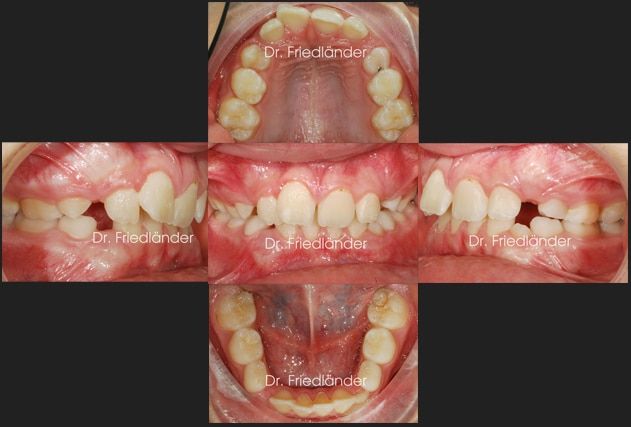

Paciente de 12 años, acude con sus padres para «arreglarse la boca», presenta arcadas dentarias estrechas, apiñamiento moderado/severo y clase II (mandíbula returuida). Después del estudio (fotografías, radiografías, modelos y exploración clínica) observamos que están a punto de cambiarse todos los dientes de leche que le quedan en boca. Se decide empezar lo antes posible con un D-Gainer del sistema de brackets de autoligado Damon, que no es más que un 2×4 que llamamos en ortodoncia, 2 brackets en los molares y 4 brackets en los incisivos con unos muelles que mantienen el espació y ayudan a la expansión.

El objetivo del 2×4 o D-Gainer es ganar espacio antes de que salgan lo caninos definitivos, así conseguimos 2 objetivos principales;

1. evitar problemas de encía, ya que un canino que sale en un lugar fuera de la arcada dentaria casi siempre suele tener problemas de encía fina, retracción de la encía etc

2.Permitir la erupción más o menos ordenada de los demás dientes y así se convierte el caso en bastante más fácil.

La paciente llevó el 2×4 (mirar la imagen de abajo) unos 6 meses, durante este tiempo empezó a recambiar sus dientes de leche gradualmente.

Detalle del antes y después del 2×4